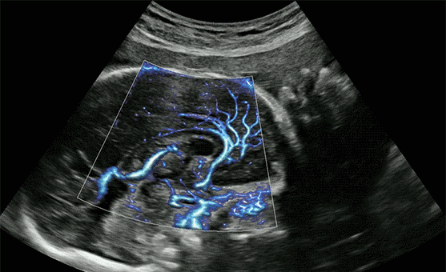

CrystalLive?是三星最新的超聲成像引擎,同時(shí)增強(qiáng)了2D圖像處理能力、3D渲染能力和彩色信號(hào)處理能力,能夠在復(fù)雜情況下提供出色的圖像性能,具備檢測外周血管、微循環(huán)血流的能力。